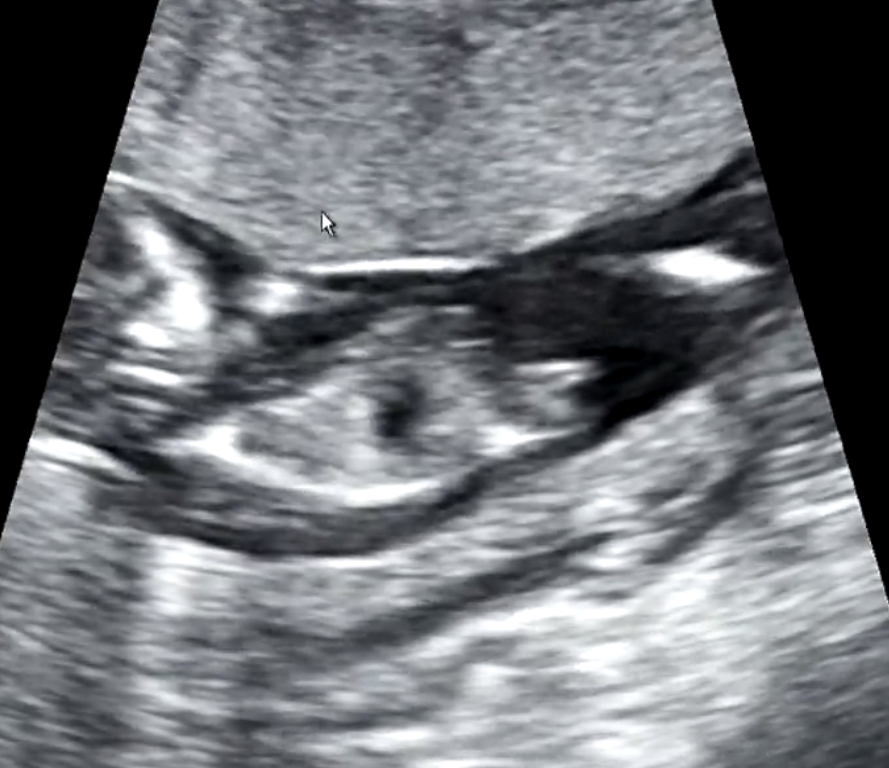

I am so anxious here! We went to the doctor yesterday for my 13 week scan and the doctor said he knew the grnder, but my husband doesn’t want to knooow! (So frustrating) we have 2 boys and want to know if I need to buy things or recycle!!

I will appreciate your help!!Attachment 40938Attachment 40939Attachment 40940